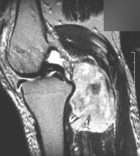

56 year old WM with right intermittent throbbing knee pain, four months ago he noticed a pop, pain, and swelling in his right knee while running, since then it has been swollen from knee to ankle, pain is getting worse

Zoom image: Radiological image Radiological image.